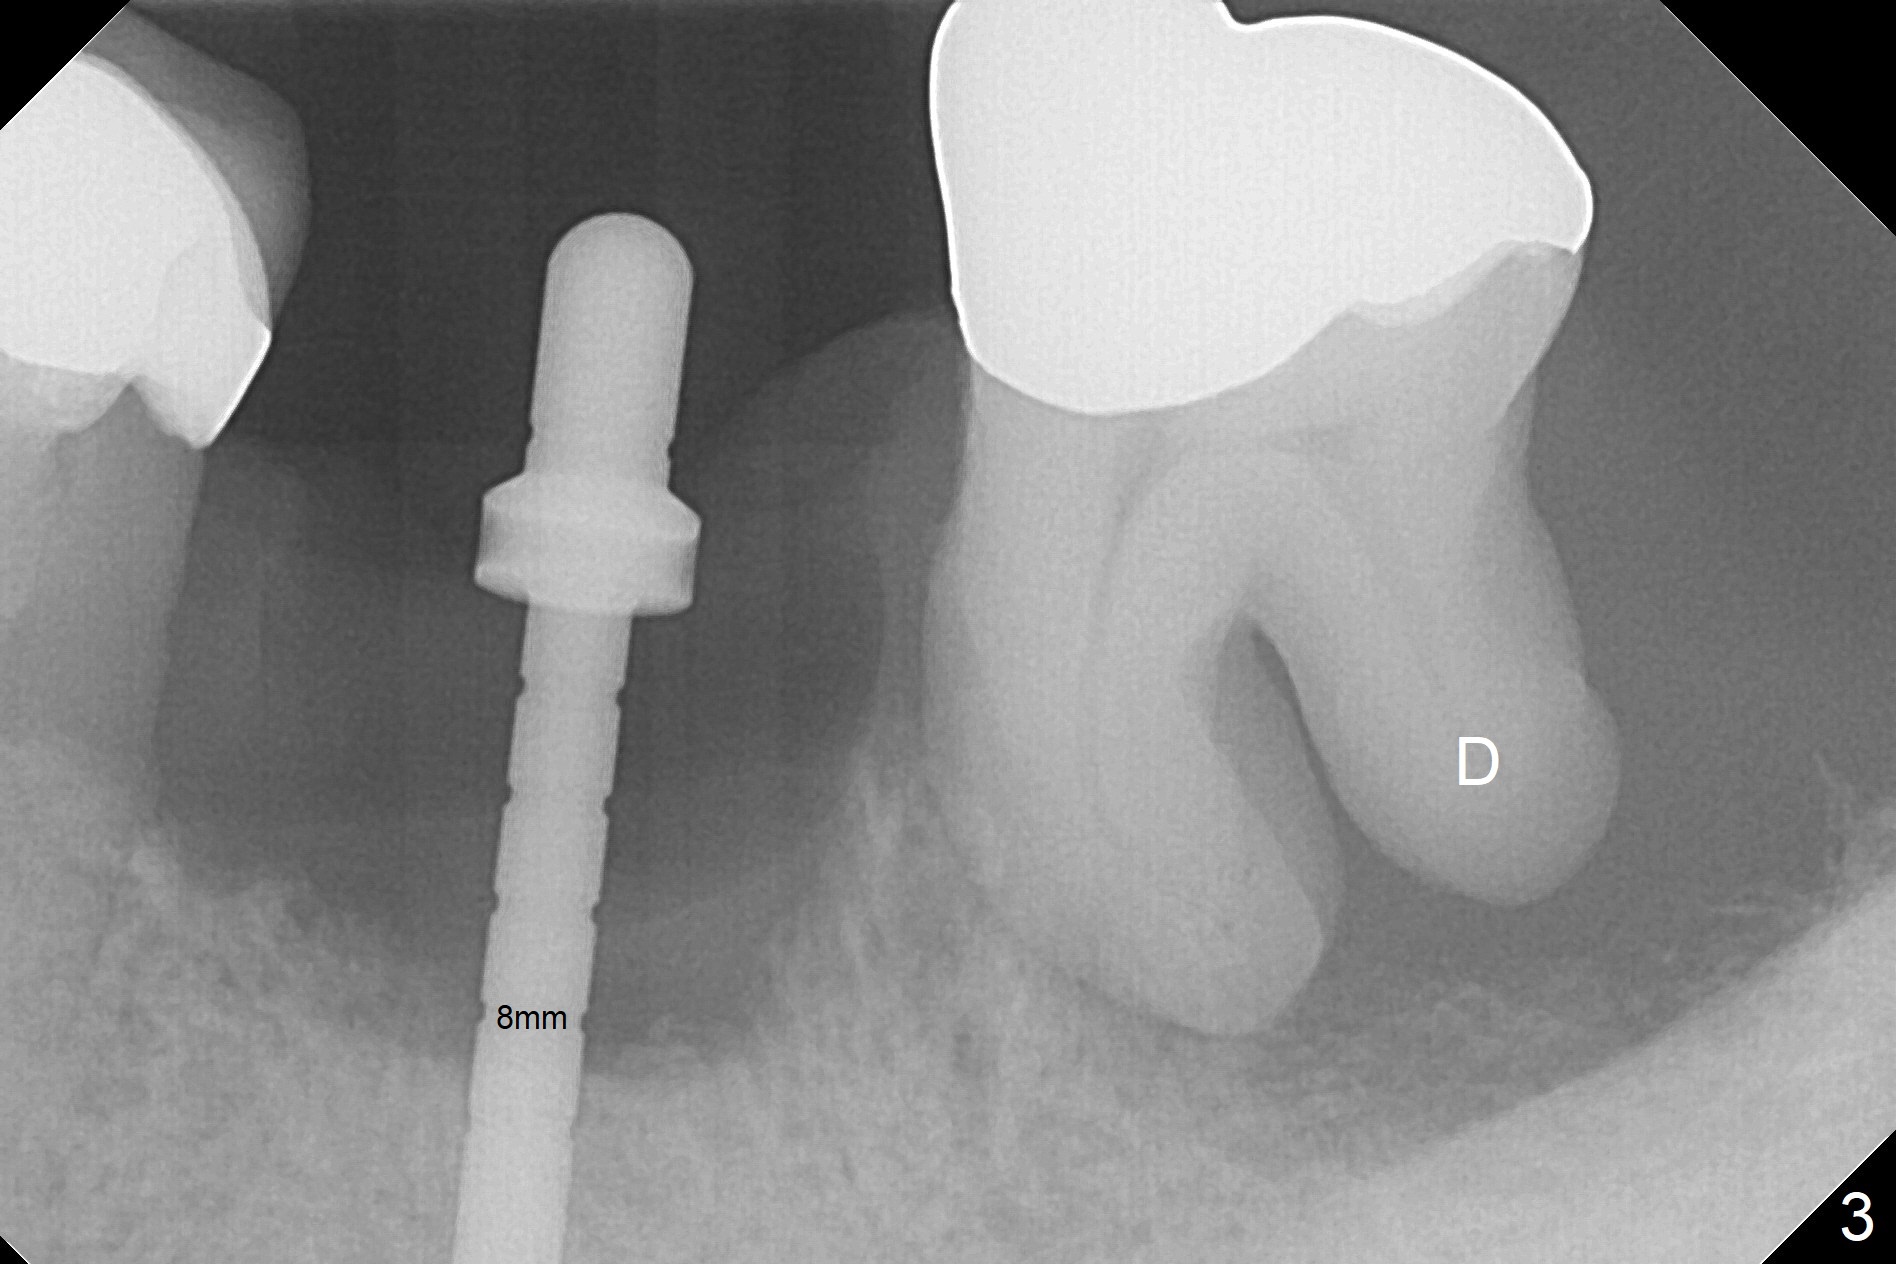

After extraction of the supraerupted tooth #19 with severe buccal gingival recession, the buccal and lingual plate are found to be lost. The sockets are fused and flat without the septum. The bone is hard and painful for the initial osteotomy with infiltration anesthesia (Fig.2). Following block anesthesia, the initial osteotomy depth extends to 8 mm (Fig.3,4). With apparent 4.9 mm clearance, the osteotomy is further extended to 10 mm. The osteotomy walls are apparently intact without severe hemorrhage after each drill. Due to the thick gingiva and severe bone loss, a 5x12 mm implant is intentionally placed 3 mm above the base of the socket bone (Fig.5,6 (yellow dashed line)). Vanilla Cortical and Cancellous allograft (Fig.6 *) is placed around the exposed implant and 7.8x5(6) mm abutment with 4 and 2 mm buccal and lingual gaps. Next collagen plug cut in strip is placed to fill the most coronal aspect of the socket (Fig.7 *). The buccal and lingual gingivae are approximated with sutures proximally. Finally periodontal dressing is applied. Since the Inferior Alveolar Canal is vague in intraop PAs (Fig.4,5), there is worry about potential nerve damage during and after osteotomy. This should be no issue if preop panoramic X-ray is reviewed with measurement (Fig.8). The bone graft appears to remain in place nearly 4 months postop (Fig.9). Two weeks later, he returns for impression. When the provisional is removed, the gingiva is unhealthy. Without the provisional and with improved oral hygiene, the gingiva is healthy one week later, but the tooth #18 is symptomatic. The latter is extracted with socket preservation (Fig.10 *). There is no apparent bone loss around the implant at #19 6.5 months post cementation (Fig.11).